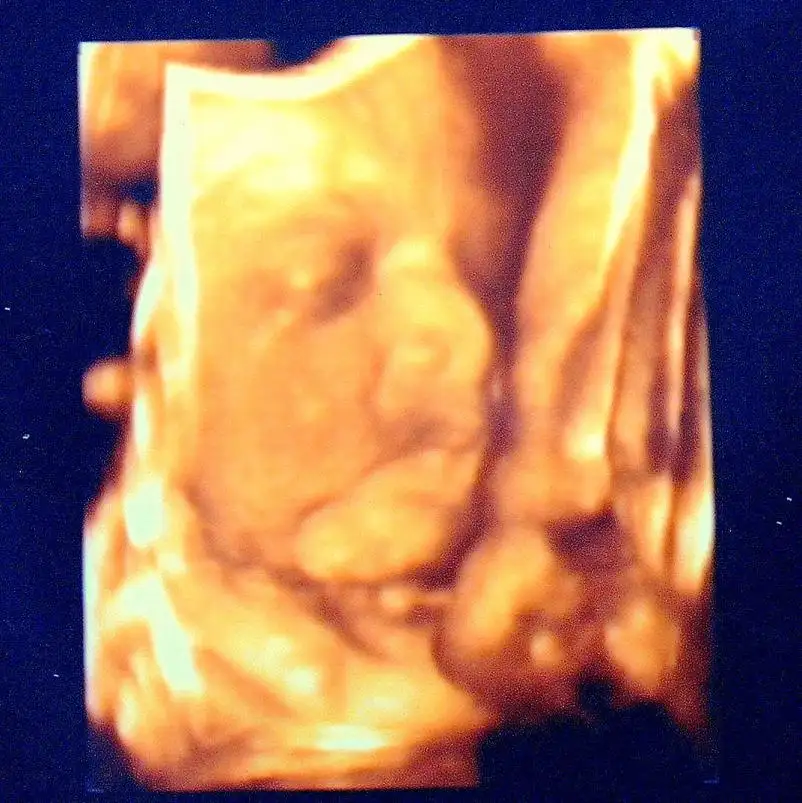

Dün doktora gittik kızım çok tatlıydı boyu 45 cm kilosu 2400 gr olmuş biraz suratımız asıktı ciddi bi kız olcak dedi doktor amcamız...herşey yolundaymış çok şükür...seni normal doğurtucam gülşah dedi doktor kafamçokkarıştı raporumuzuda verdi bundan sonra 15 de bir görüşcez dedi 25 aralık'a gün verdi..bizden şimdilik bu kadar

buda pozumuz...